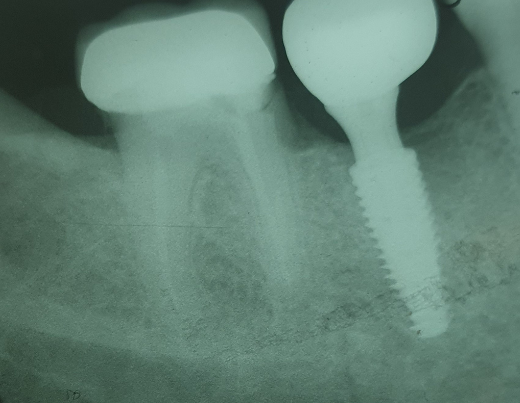

Veja alguns casos de sucesso